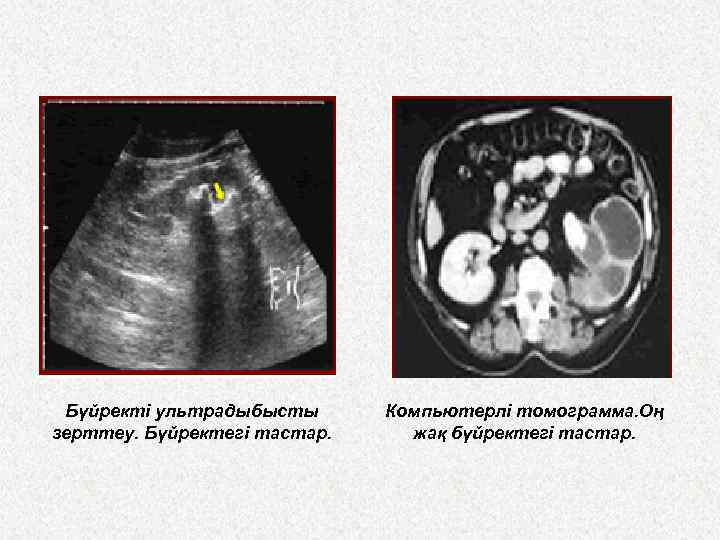

Нефролитаз кезіндегі УДЗ бүйректің контурларын, бүиректің тостағанша түбекшелердің жалпы жағдайын көрсетеді. Тастың көлемін формасын, тостағаншалар дың қалыптыдан өзгергендігін көрсетеді.

• Бүйректі ультрадыбыспен тексеру (УЗИ). • Өлшемі 3 мм-ден ірі конкременттер жақсы көрінеді. УЗИ кезінде несеп ағуының бұзылу дәрежесін анықтауға болады — конкрементті жұка (1 -2 мм) сұйықтық қабаты қоршаған кезде — ең аз дәрежесі. Егер конкремент бүйрек тостағаншасынан шығатын ағынды бөгесе, бұл тостағаншаның 10 мм-ден аса ұлғайғаны, бұл ондағы сұйықтыктың көлемі 0, 6 мл-ге немесе одан да астам мөлшерге сай келетінін білдіреді. Астауда, астау-несепағар сегментінде немесе несепағарда орналасқан конкремент бүйректен шығатын ағынды тұтас бөгейтін болса, тостағаншаастаудың қабырғасы жаппай ұлғаяды, оны УЗИ-де оңай анықтайды.

Бүйректі ультрадыбысты зерттеу. Бүйректегі тастар. Компьютерлі томограмма. Оң жақ бүйректегі тастар.